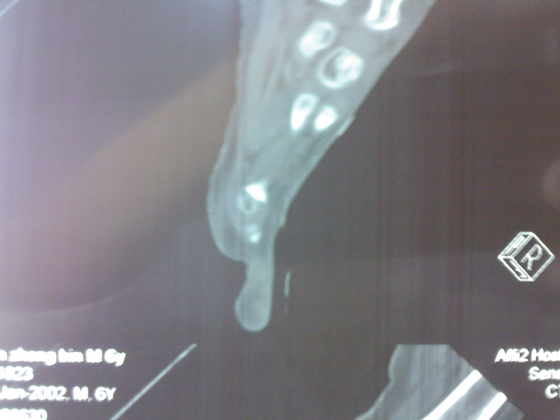

把病理送浙一医会诊后诊断为:骨外软骨瘤。同时做了CT检查。暂未予治疗。

今天把创面情况跟CT发上请大家看看。

继续发CT片